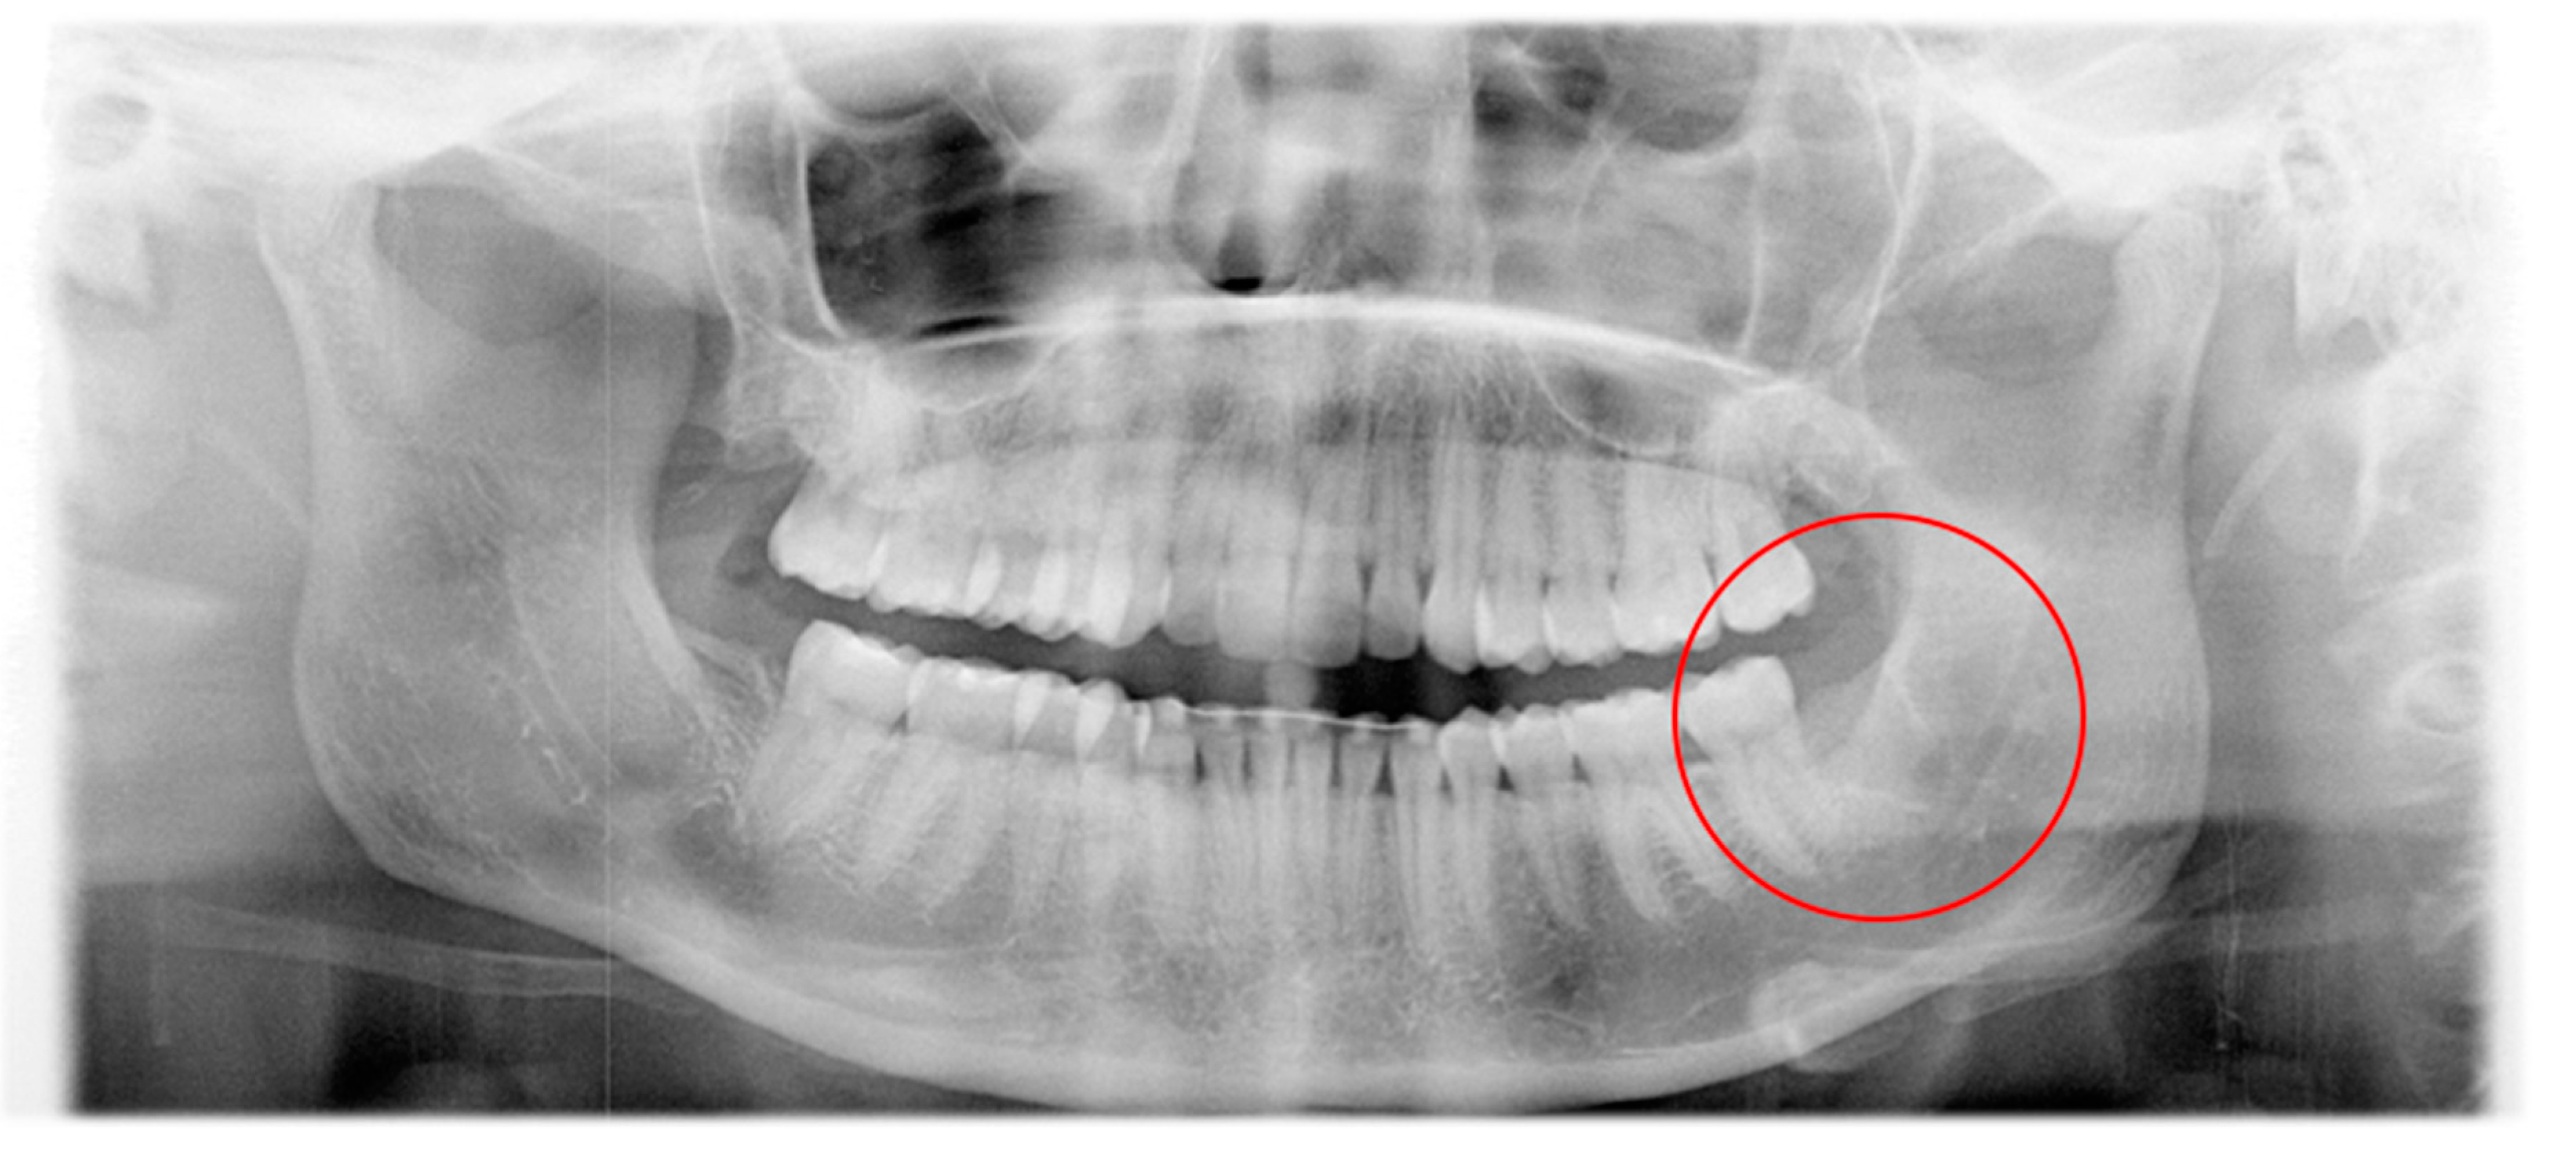

2. Patient and Methods